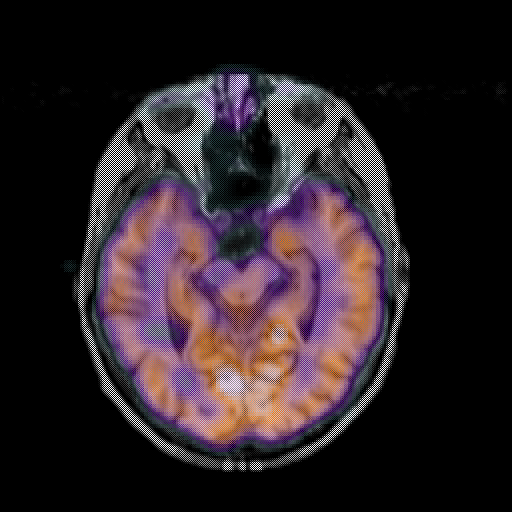

overlay: Slice 22

Slice 22

MRCBFCBF with

T1PDT2T1PDT2